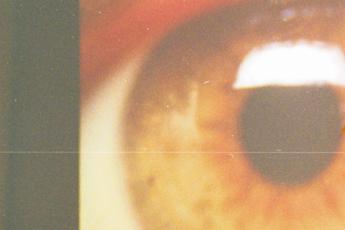

(Adnkronos) – Era dicembre 2023 quando veniva annunciato che Holostem, l'azienda biotech di Modena nata per sviluppare terapie avanzate a base di cellule staminali e impegnata da anni per dare una speranza di terapia ai 'bambini farfalla', affetti da una rara malattia genetica, l'epidermolisi bollosa, era ufficialmente salva. Scongiurata la liquidazione, infatti, con l'intervento del ministero del Made in Italy e delle Imprese (Mimit) era stato avviato il percorso di acquisizione da parte della Fondazione Enea Tech e Biomedical. Il 2024 è stato l'anno del rilancio a livello internazionale sul fronte dello sviluppo di terapie cellulari e geniche per malattie rare e senza rimedio. Un rilancio che passa anche da una terapia salva-cornea. Il 7 gennaio 2025, al Centre Hospitalier Universitaire de Liège, il professore Bernard Duchesne ha effettuato con successo la biopsia alla cornea di un giovane paziente che aveva subito un'ustione causata da agente chimico durante un'aggressione. Il giorno successivo alla biopsia, il team di esperti dell'officina farmaceutica Gmp della Holostem, nel Centro di medicina rigenerativa dell'università di Modena e Reggio Emilia, è stato in grado di estrarre le cellule staminali limbari della cornea per la preparazione della terapia Holoclar. Una accurata conta, estrazione e crescita delle staminali limbari è la condizione essenziale per lo sviluppo della terapia cellulare destinata all'impianto sul paziente, che è possibile ad oggi mettere in atto soltanto nei laboratori di Holostem. Altri pazienti sono già in lista per l'avvio della terapia a febbraio. La terapia Holoclar è stato il primo prodotto di terapia cellulare al mondo che ha avuto nel 2015 il Conditional Approval per l'immissione in commercio in Ue e nel Regno Unito, rispettivamente dagli enti regolatori Ema (Agenzia europea del farmaco) e dalla britannica Mhra (Medicines and Healthcare products Regulatory Agency), ottenendo poi la Full Marketing Authorization nel primo semestre del 2024. Merito del risultato, ha sottolineato l'Ad della società, Alessandro Padova, deve essere riconosciuto al team di Holostem che ha lavorato incessantemente, con passione e impegno, per mettere di nuovo a regime i laboratori altamente specializzati dell'officina Gmp e far ripartire la produzione del prodotto cellulare terapeutico. La commercializzazione di Holoclar, spiegano da Holostem in una nota, rappresenta l'avvio del nuovo piano industriale di Holostem che inoltre "prevede la creazione di attività ed investimenti finalizzati alla scoperta e sviluppo di terapie innovative personalizzate per malattie rare ad oggi senza terapia risolutiva, con un approccio di open innovation attraverso importanti partnership strategiche con centri ospedalieri italiani ed europei". Il valore dell'innovazione e competitività dell'azienda, prosegue la nota, è stato riconosciuto anche dalla Commissione europea che ha selezionato Holostem per avere accesso ai finanziamenti Ipcei (Importanti Progetti di Comune Interesse Europeo) Med4Cure, in quanto una tra le 13 aziende europee in grado di perseguire l'obiettivo di sostenere la realizzazione di progetti innovativi e di rilevanza strategica per salute e sanità, al fine anche di migliorare la qualità e l'accesso alle cure del paziente. "Senza l'apporto di ciascuno dei componenti del Consiglio di amministrazione ed il contributo del Collegio dei sindaci non sarebbe stato possibile, in un contesto estremamente complesso, arrivare alla definizione del piano industriale della società e così permettere all'azienda di ripartire nelle attività di produzione e ricerca – commenta il presidente della Holostem, Francesco Vetrò, manifestando soddisfazione per il risultato raggiunto – Il risultato, tuttavia, non sarebbe stato neppure lontanamente alla portata se la Fondazione Enea Tech e Biomedical ed il Mimit non avessero con lungimiranza salvaguardato e rilanciato un'azienda unica nel settore in Italia e all'estero". E, ricorda ancora, "nulla si sarebbe potuto realizzare se non vi fosse stato l'iniziale apporto di risorse della Chiesi Farmaceutici e senza la partnership con l'università di Modena e Reggio Emilia". —[email protected] (Web Info)